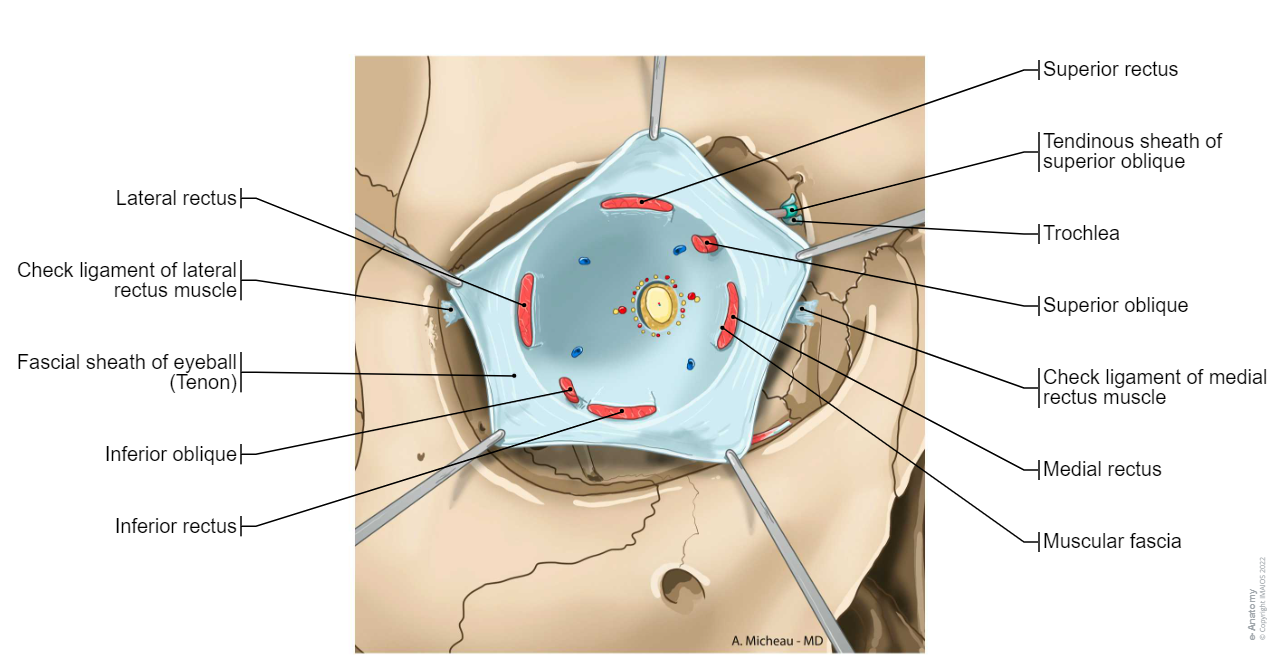

Fascial sheath of eyeball (Tenon) - Extraocular muscles; Extrinsic muscles of eyeball: Superior rectus, Inferior rectus, Medial rectus, Superior oblique, Trochlea, Inferior oblique

Fascial sheath of eyeball (Tenon) : Extraocular muscles; Extrinsic muscles of eyeball